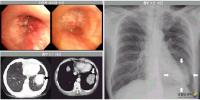

Æó¾Ï - Áø´Ü¹æ¹ý

Æó¾Ï Áø´Ü ¹æ¹ý¿¡´Â ¿©·¯ °¡Áö °Ë»ç°¡ Àִµ¥, Æó¾ÏÀ¸·Î ÀǽɵÇ...